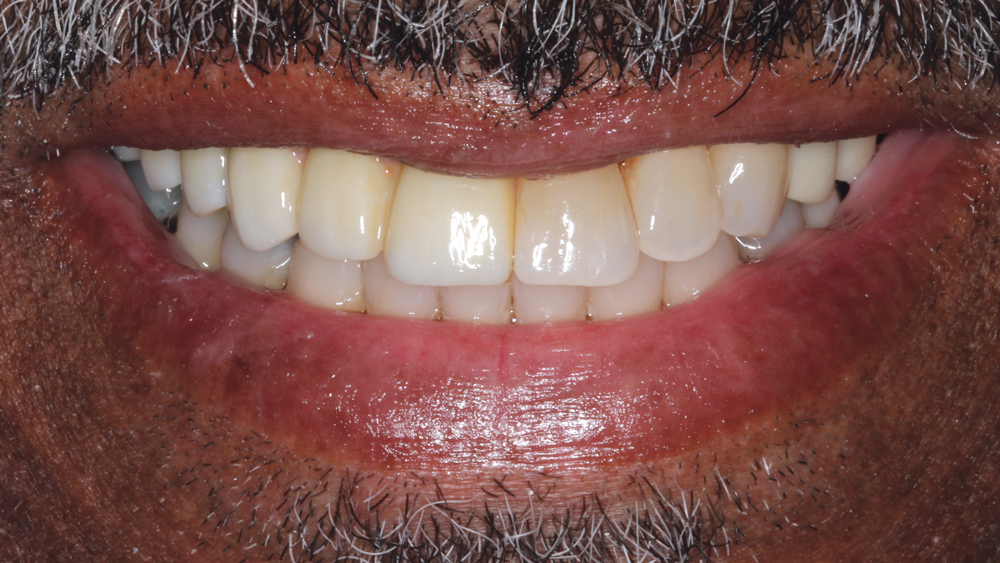

BruxZir Solid Zirconia has proven to be extremely strong yet compatible with opposing natural dentition; the material exhibits minimal wear on the opposing enamel. Its color and shading are extremely natural in appearance, and I have no concerns about chipping or cracking of the material over time. The final seating of the prosthesis was straightforward, and I have confidence that the material is a long-lasting solution. Weldon was thrilled with the final restoration, as we were able to surpass his expectations and provide him with a fixed, functional, esthetic result.

Understanding the foundation required to predictably place dental implants, including effective extraction techniques, socket management and grafting procedures, has improved the prognosis. Working with talented and well-trained laboratory technicians helps us plan the final prosthetic result prior to any surgical procedure. Innovative laboratory techniques and materials provide outstanding functional and esthetic results. As for Weldon, his BruxZir implant bridge ensures an excellent long-term prognosis as well as restored esthetics in an area that was compromised by tissue loss prior to treatment.